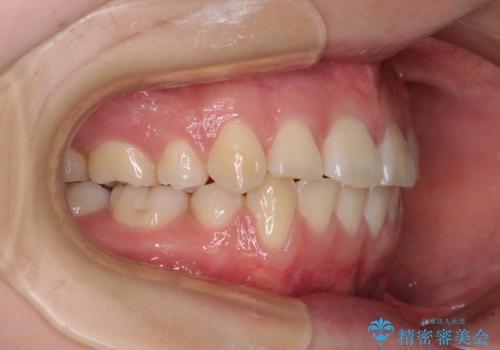

- 上下前歯の叢生と八重歯を気にして来院された患者様です。

前歯部叢生のスペースを獲得するため、上下顎左右小臼歯各1歯を抜歯することとしました。